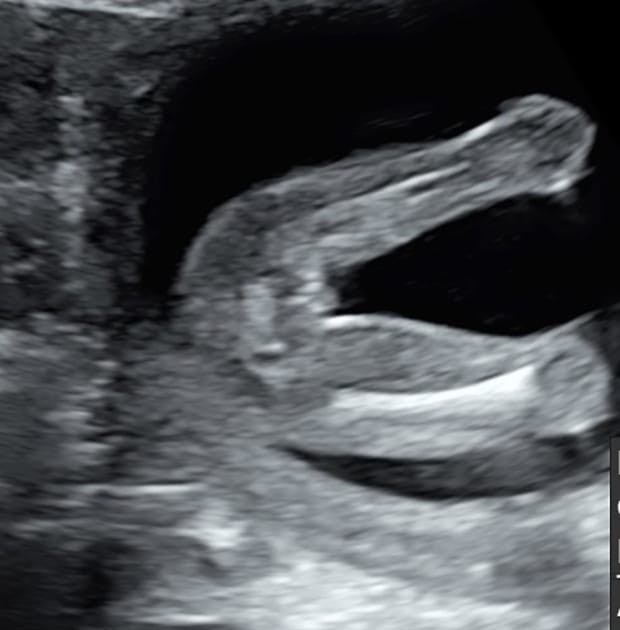

ベビーナブが気になる気になる テーマ: 暮らしを楽しむ () カテゴリ: マタニティ🤰 早速ですが、、、 前の投稿でも申しました通り現在第二子を授かっております🌿 1人目のときもそうでしたが、、 やはり性別が気になる気になる笑笑 いろいろ baby nub(ベビーナブ)ってなに? アメリカをはじめとする海外では、"The Nub Theory"といって、 11~12週頃の横向きのエコーに映る、突起の角度で男の子か女の子かを予想する。 という理論が割と知られているそうです。エコーの写り方で12wじゃ確定や判断 ができない場合があります Nubがうつってないと判断できません~ Nubがはっきりうつってると自分でも 性別判断出来ると思います\ (ϋ)/ 私はエコー見てるときにnub見えて あ、女の子って思いました (∩ˊᵕˋ∩

R先生というのは北海道の産婦人科医で 赤ちゃんが11〜13wくらいのときにエコーに映る ベビーナブというものの角度で 性別を判定できるという凄い方 普通、性別が分かるのはwくらいだったり 赤ちゃんが隠してしまってエコーで映らないと もっと ベビーナブについて。12週の時のエコーです。画質が悪く見にくいかとは思いますが、男の子と女の子どっちの可能性が高いといえますか?胎児の性分化は 個人差がありますが週から26週にかけて 完了します。現在は 胎児の組織を採取し いつから&見方は? お腹の赤ちゃん男の子か女の子かがわかる? 女の子のベビーナブは、身体の発達が進むとクリトリスになる部位です。 エコー写真に写った突起が背骨に対して並行で、足に向かって伸びていれば女の子という見立てになります

もしこれがナブなら、背骨に対して平行なので女の子かなと思うけどなんか違うような。 先生にベビーナブのこと聞けば良かったんだけど聞けなかったです 次の健診は4週間後なので、もうナブは見れません 残念 妊娠中の経過の記録" ベビーナブ "でした!! 男の子と女の子では、9w〜12w頃の横向きエコーで見た生殖器の角度が異なるみたいでそれで判別、予想する という海外ではよくある判定方法! 女の子ベビーナブ写真 通っている産婦人科の先生に『ナブを見てもらいたいから』と伝えるのはあまりお勧めできません。 考え方の違いだったり、専門の先生に注文をつけることに嫌な顔をする先生もいます。

ベビーナブとは?女の子男の子の性別が早くから分かる ベビーナブには妊娠14週ごろまで男の子でも女の子でも大きさは同じで、突起物があるので男の子に見えがちです。 ベビーナブは正確? ベビーナブで性別が分かるのは妊娠13~14週頃まで。ベビーナブについてです!ベビーナブの男の子、女の子の違いはなんでしょ ベビーナブについてです! ベビーナブの男の子、女の子の違いはなんでしょう? もし見分けられる方いたら教えてください🙏 あと皆さんはいつ頃性別確定しましたか?🤔Babynub ベビーナブ 早期性別判定について調べていた時、babynubという言葉を知りました。 胎児の横向きからの突起の角度で性別を判断するというものです。 が、素人の私にはエコー写真を見てもさっぱり分かりませんでした。 確かに背骨に対して平行